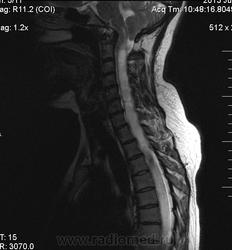

Сирингомиелия шейно-грудной локализации? Аномалия Арнольда-Киари I. Платибазия.

здоровенная сирингогидромиелитическая киста (по видимому, "высокого давления"), мальформация Киари 1.   также имеются признаки внутренней окклюзионной гидроцефалии.

Убедительных данных за патологическое накопление контрастного препарата не выявлено. Кисты с повышенным содержанием белка (?), может быть бывают атеромы в области мягких тканей шеи (гиперинтенсивные по Т1 между мышцами шеи справа)?